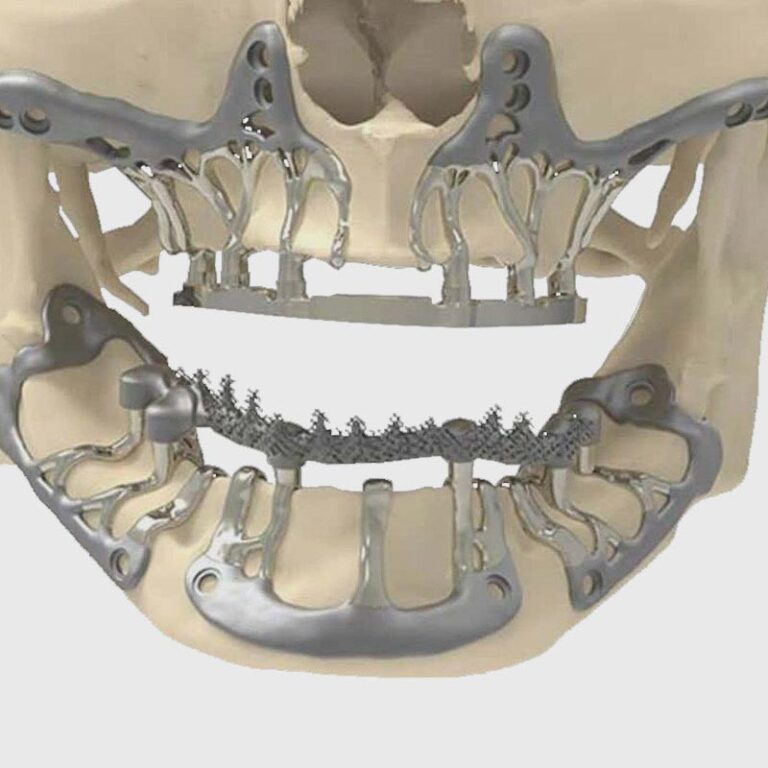

Especialmente diseñados para quienes no tienen suficiente hueso y no desean someterse a injertos. Este tipo de implante se coloca sobre el hueso, bajo la encía, adaptándose a la anatomía del paciente.

👉 Solución eficaz sin cirugía regenerativa.

Ideales para casos de atrofia ósea severa en el maxilar superior. Se anclan directamente al hueso cigomático (pómulo), permitiendo fijación segura sin injertos óseos.

👉 La alternativa avanzada cuando otros tratamientos no son viables.